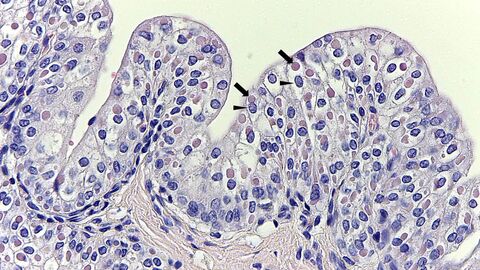

Bei toten Tieren gibt die Obduktion näheren Aufschluss über die Erkrankung. Durch die feingewebliche (histologische) Untersuchung lässt sich eine Staupeerkrankung mit gewisser Sicherheit – durch den Nachweis von Einschlusskörperchen in Virus-infizierten Zellen (Abb. 1) - diagnostizieren. Der sicherste Nachweis gelingt mittels real-time RT-PCR aus Organmaterial.

Eosinophile intrazytoplasmatische Einschlusskörperchen im Übergangsepithel der Harnblase eines Fuchses

Abb. 1: Zahlreiche eosinophile intrazytoplasmatische Einschlusskörperchen (Pfeil) im Übergangsepithel der Harnblase eines Fuchses. Basophile Zellkerne sind mit Pfeilspitzen gekennzeichnet. Präparat aus der Diagnostik des Hessischen Landeslabors.